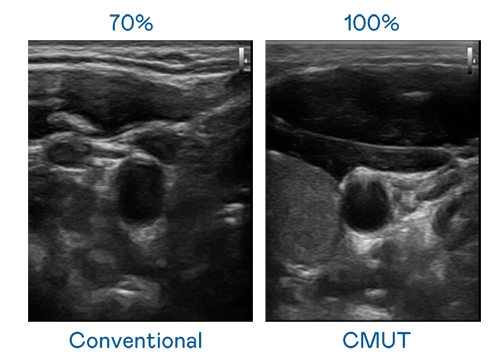

CMUT 技术是一种用电容式微机电元件来产生超音波讯号的技术。与传统 PZT 压电式技术相比,CMUT 频宽增加 30%,更宽频的超音波讯号让影像解析度大幅提升,是实现高影像品质医疗超音波扫描、促进精准医疗发展的关键技术。

超音波影像的解析度高低,首先取决于探头能发出的讯号频宽。AG真人平台 CMUT 可提供高清晰的超音波讯号,提供高频宽、高灵敏度、影像纹理细节更高的超音波影像,协助医护人员缩短影像判读时间及利用精准的医疗影像进行诊断。